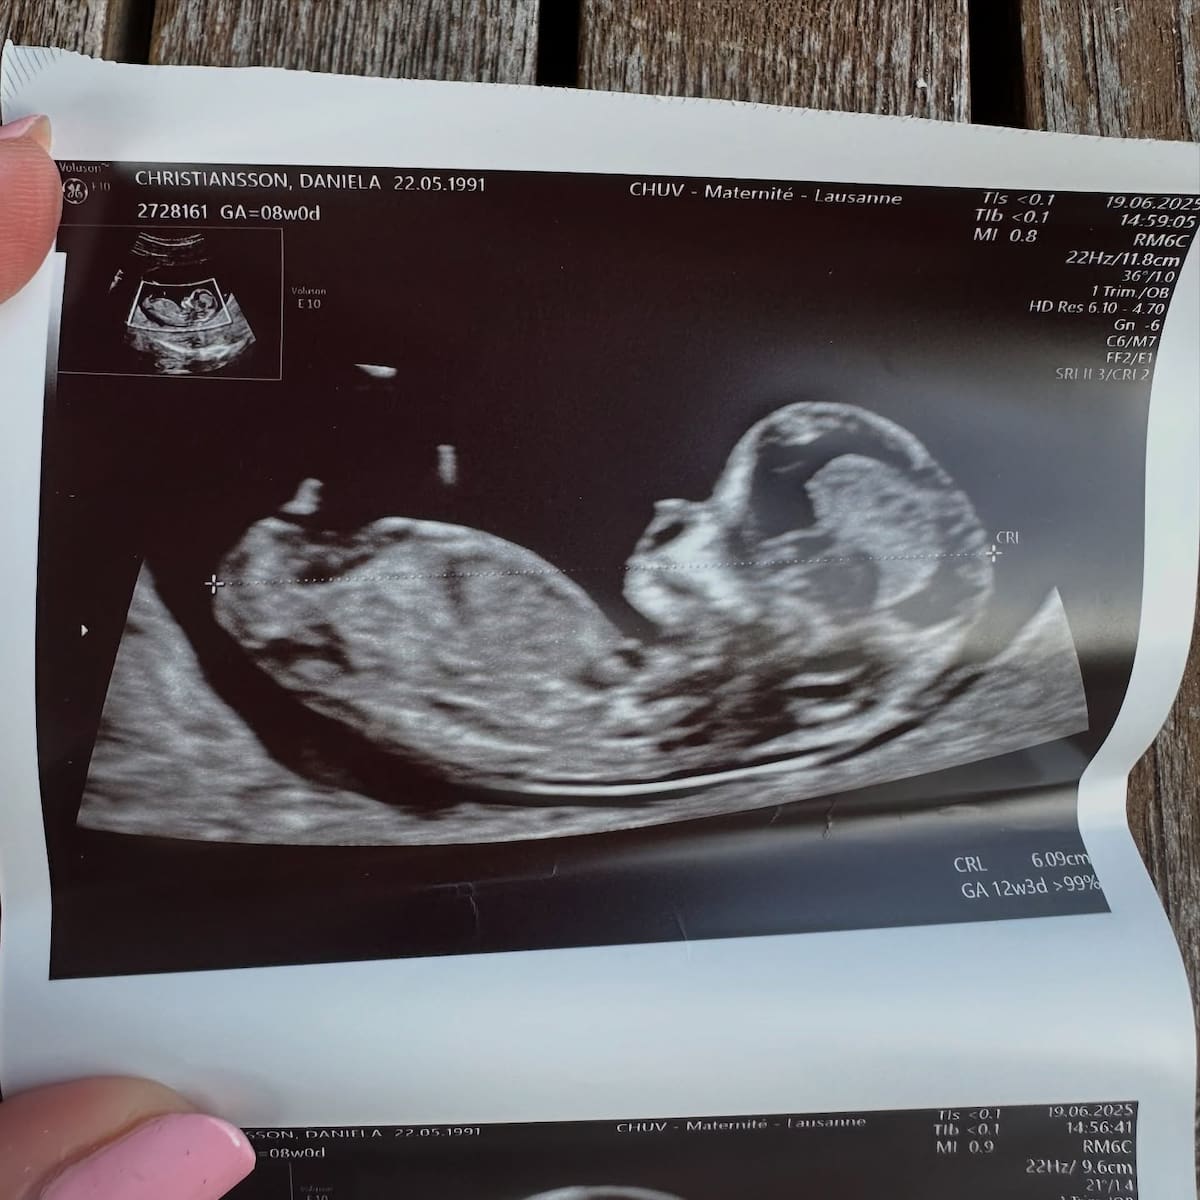

Además, mostró la primera imagen oficial de su nuevo bebé: una ecografía que data de fecha 19 de junio. Según especificó Daniela, tiene un embarazo de aproximadamente 13 semanas.

Hace dos años la pareja recibió la llegada de Elle, su primera hija juntos, con mucha emoción de formar una familia juntos. Este nuevo integrante sería el hijo número cinco de Maxi López, ya que tiene a Benedicto, Constantino y Valentino con Wanda Nara.